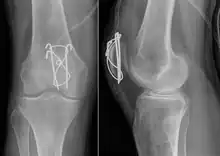

A fracture of the patella seen on a lateral view | |

Most patella fractures are transverse or comminuted, hence the quadriceps mechanism is disrupted and they are treated by a combination of wires in a tension band construct. This unites the fractured bones, reconstructing the straightening mechanism of the leg.[5][6]